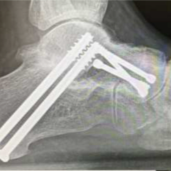

Deformity Correction Cavus Foot Reconstruction Cavus Foot Reconstruction Triple Fusion Triple Fusion Charcot Beaming Charcot Beaming Double Fusion Double Fusion Flatfoot Reconstruction Flatfoot Reconstruction Subtalar Fusion Subtalar Fusion